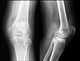

Degenerative arthritis

Osteoarthritis (OA) is a type of joint disease that results from breakdown of joint cartilage and underlying bone. The most common symptoms are joint pain and stiffness. [Source: Wikipedia ]